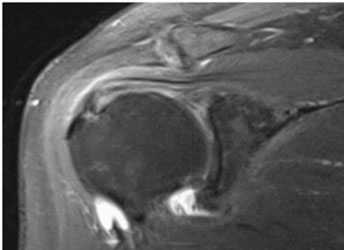

Наиболее информативными являются инструментальные методы исследования. Рентгенография используется редко, поскольку этот метод позволяет оценить лишь состояние костной ткани, а о повреждении связочного аппарата с ее помощью можно судить косвенно. КТ и МРТ позволяют комплексно оценить состояние плечелопаточного сочленения, определить состояние мягких тканей, расстояние между костными структурами. Эти методы позволяют не только выявить болезнь, но и определить оптимальную тактику лечения.

Импинджмент-синдром.а. МРТ плечевого сустава, б. рентгенография плечевого сустава.